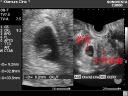

検査と診断 超音波検査でかなり小さな筋腫まで発見できるようになり、妊婦検診で初めて診断されて驚かれる方もいらっしゃいます。子宮筋腫のある場所によっては、卵巣腫瘍や子宮周囲の腫瘍と鑑別しにくいこともあり、カラードップラー法やMRIなどを用いて診断することも有ります。

また、妊娠子宮の部分的な収縮があたかも小さな筋腫のように診えることもあるので何回か超音波診断を繰り返すこともあります。